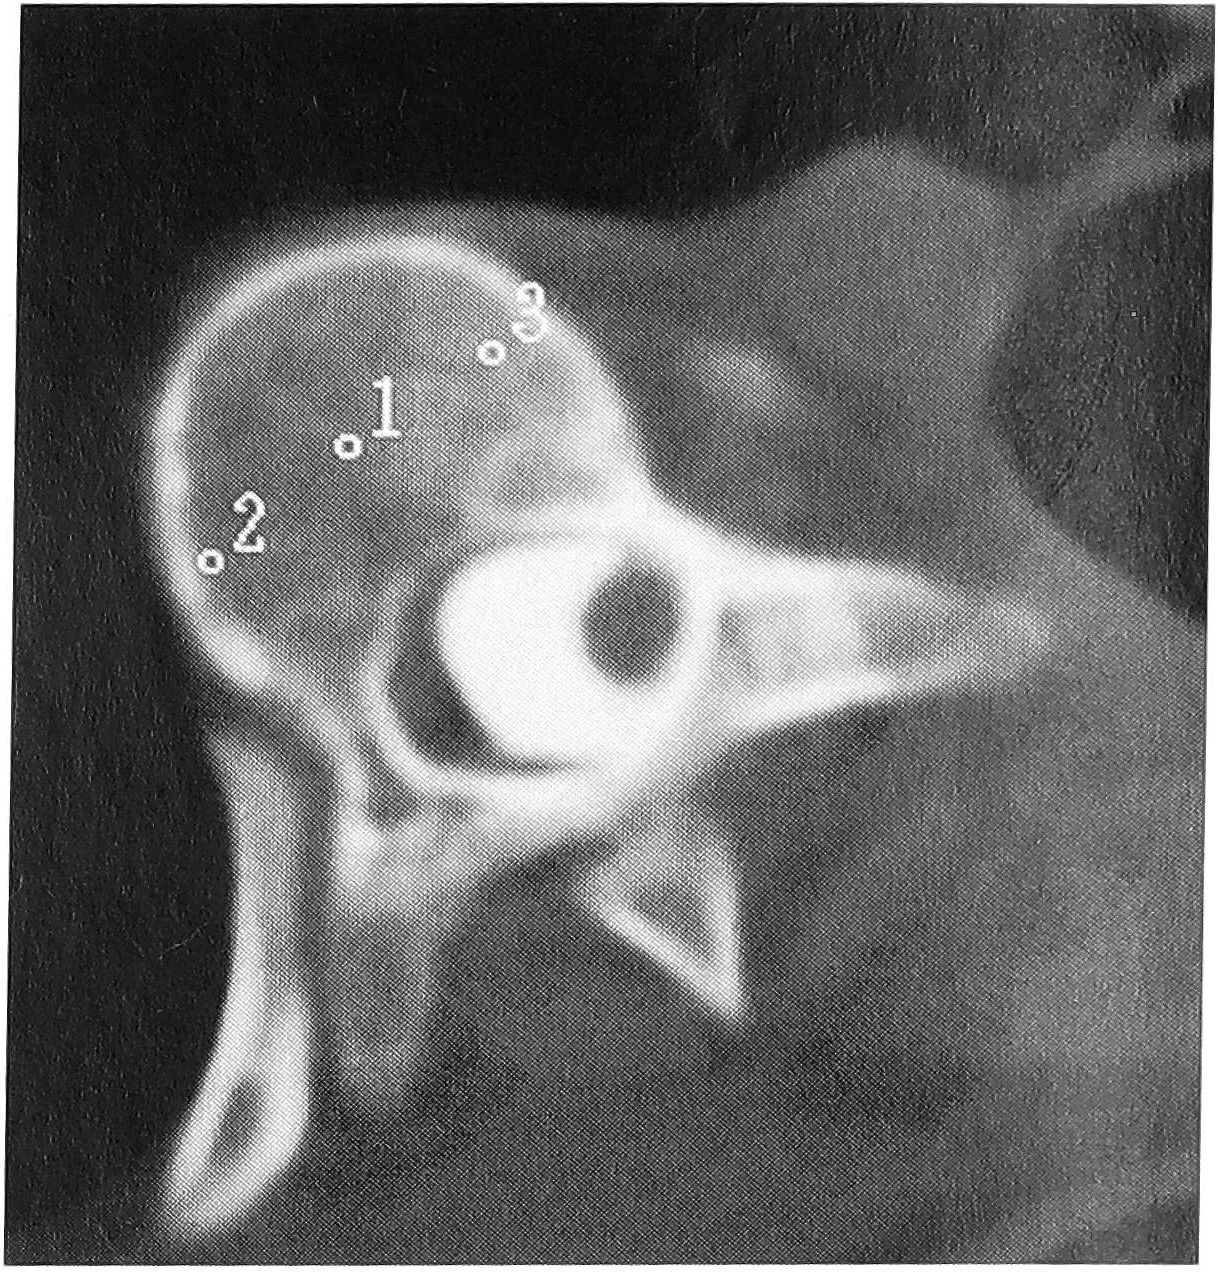

На уровне вершинного позвонка первичной дуги сколиотической деформации значимых различий в костной плотности, измеренной до и непосредственно после оперативного лечения, не обнаружено. Вместе с тем выявлена следующая закономерность: средняя величина костной плотности на вогнутой стороне деформации значимо больше, чем на выпуклой, как до, так и после оперативного лечения. Более высокая плотность костной ткани на вогнутой стороне деформации определяется и визуально при КТ (рис. 11).

Рис. 11. Вершинный позвонок первичной дуги деформации: плотность костной ткани на вогнутой стороне выше, чем на выпуклой.

Достоверных различий при сравнении показателей костной плотности в разных точках верхнего и нижнего нейтральных позвонков до и непосредственно после оперативного лечения не найдено. По вогнутой стороне деформации костная плотность нейтральных позвонков несколько ниже, чем по выпуклой, причем это различие наиболее выражено на уровне верхнего нейтрального позвонка после оперативного лечения (что, вероятнее всего, связано с изменением его положения в пространстве). В центре тела у верхнего нейтрального позвонка костная плотность значительно выше, чем у нижнего, как до, так и после оперативного лечения (практически на одинаковую величину).